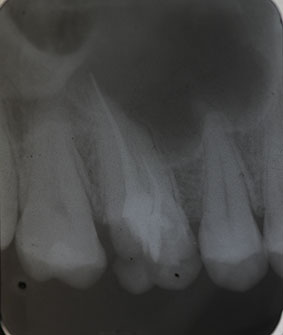

Nach Darstellung aller Wurzelkanaleingänge wird in einem zweiten Schritt das frakturierte Wurzelkanalinstrument dargestellt (Abb. 3 u. 4). Hierfür verwenden wir den Aufsatz 3E des Tigon+. Durch die schmale und lange Form des Instruments erreichen wir einen tiefen und schmalen Zugang.

Sofern es sich um ein kleines Frakturstück handelt, kann es durch aktive Übertragung von Energie des Ultraschalls zu einer Lockerung des Fragments kommen. Lockert es sich nicht, so „umkreist“ man das Instrument vorsichtig, um es anschließend mit einer Spritze gefüllt mit Palavit G zu greifen, zu fixieren und zu entfernen (Abb. 5). Nach Entfernung des Instruments erfolgt eine Kontrollaufnahme (Abb. 6).